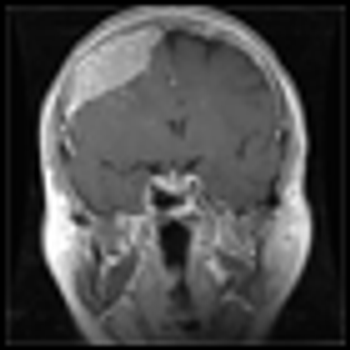

Intracranial neoplasms can arise from any of the structures or cell types present in the cranial vault, including the brain, meninges, pituitary gland, skull, and even residual embryonic tissue. The overall annual incidence of primary brain tumors in the United States is 14 cases per 100,000 population.

Brain metastases are the most common type of brain tumor in adults and are an increasingly important cause of morbidity and mortality in cancer patients. In recent years, important advances have been made in the diagnosis